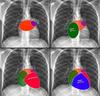

Heart borders on a CXR

How to identify pulmonary trunk on CXR?

ABove the left main bronchus but below the aortic knuckle

Features of right atrial enlargement on a chest xray?

Occupies more of the retrosternal space

How to identify the heart borders on a lateral chest xray?

Right heart border anteriorly

Left atrium posteriorly at the top, ventircle down the bottom

(remember they are closest to the oesophagus)